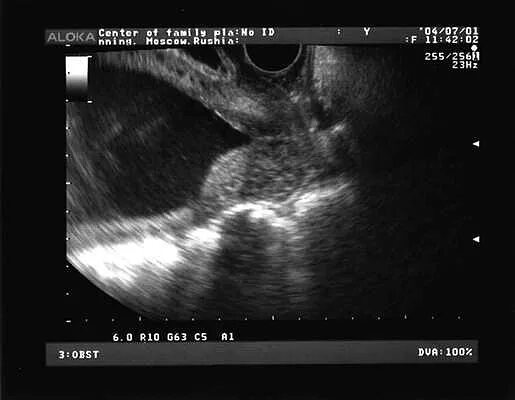

Внутренний зев воронкообразно